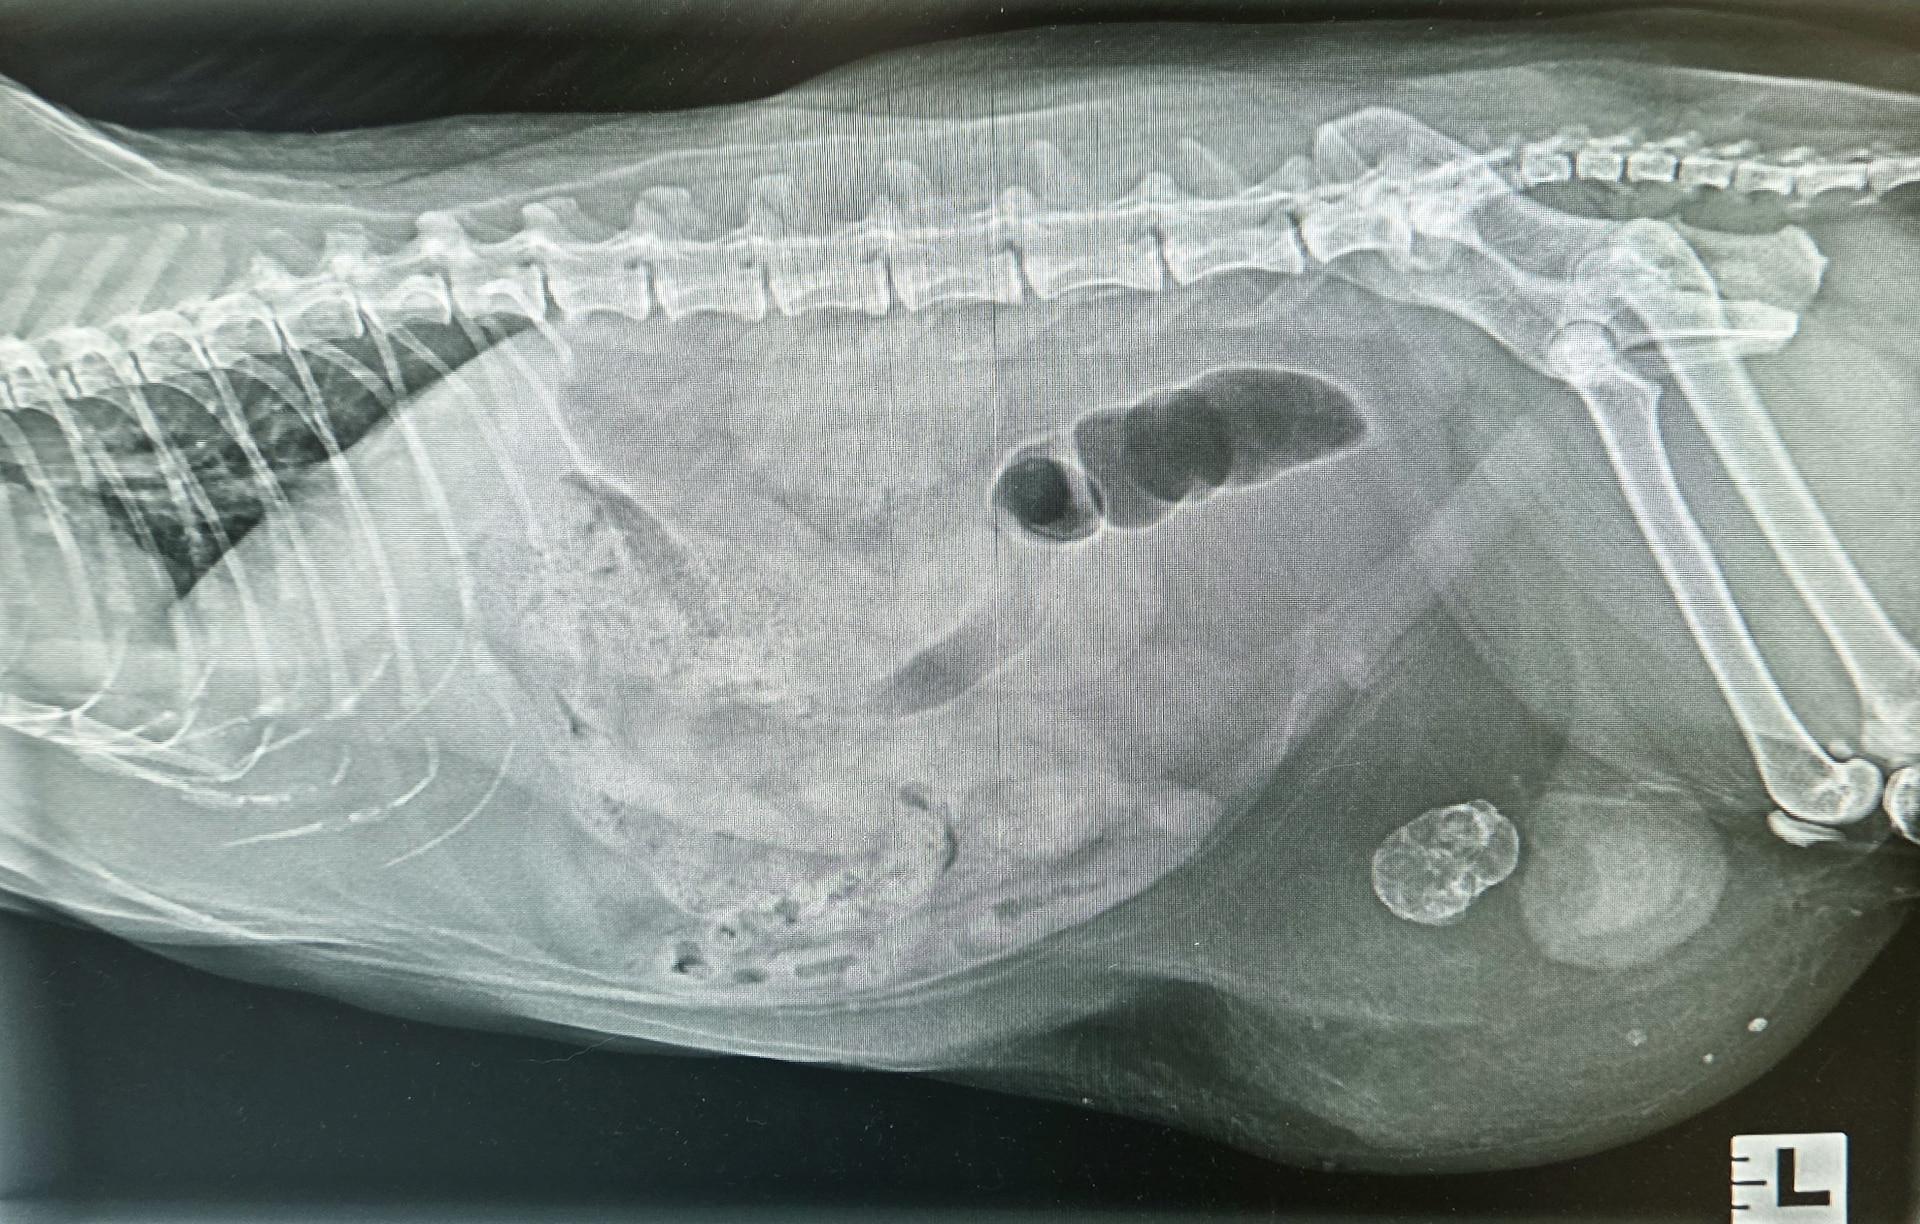

Belle-Bulle came to see us with signs of a urinary tract infection. X-rays were done to look for possible bladder stones, and boy were we in for a surprise!

Turns out her bladder was sitting outside her body wall in a fat pocket under the skin, and there was a strange mass in front of it! Surgery was performed, and as it turns out at some point the bladder had passed out through a hernia in the body wall and the hernia had healed, trapping the bladder outside her body. This had likely happened quite some time ago. There was also a strange mineralized mass sitting in front of it.